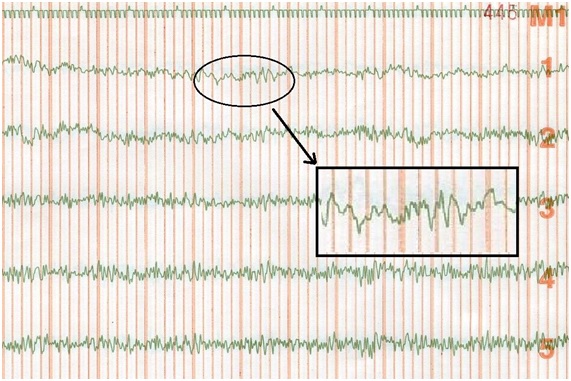

A continuación una de las paginas de nuestros antiguos EEG dibujados por las plumillas de tinta.

En la primera linea una plumilla dibujaba el paso del tiempo. La muesca hacia arriba marcaba el inicio de los segundos. Las muescas hacia abajo dividian los segundos en 10 partes iguales.

Cada linea representaba una región de la cabeza. La digitalización de la señal convirtio las lineas en paginas y paginas de pilas de numeros.